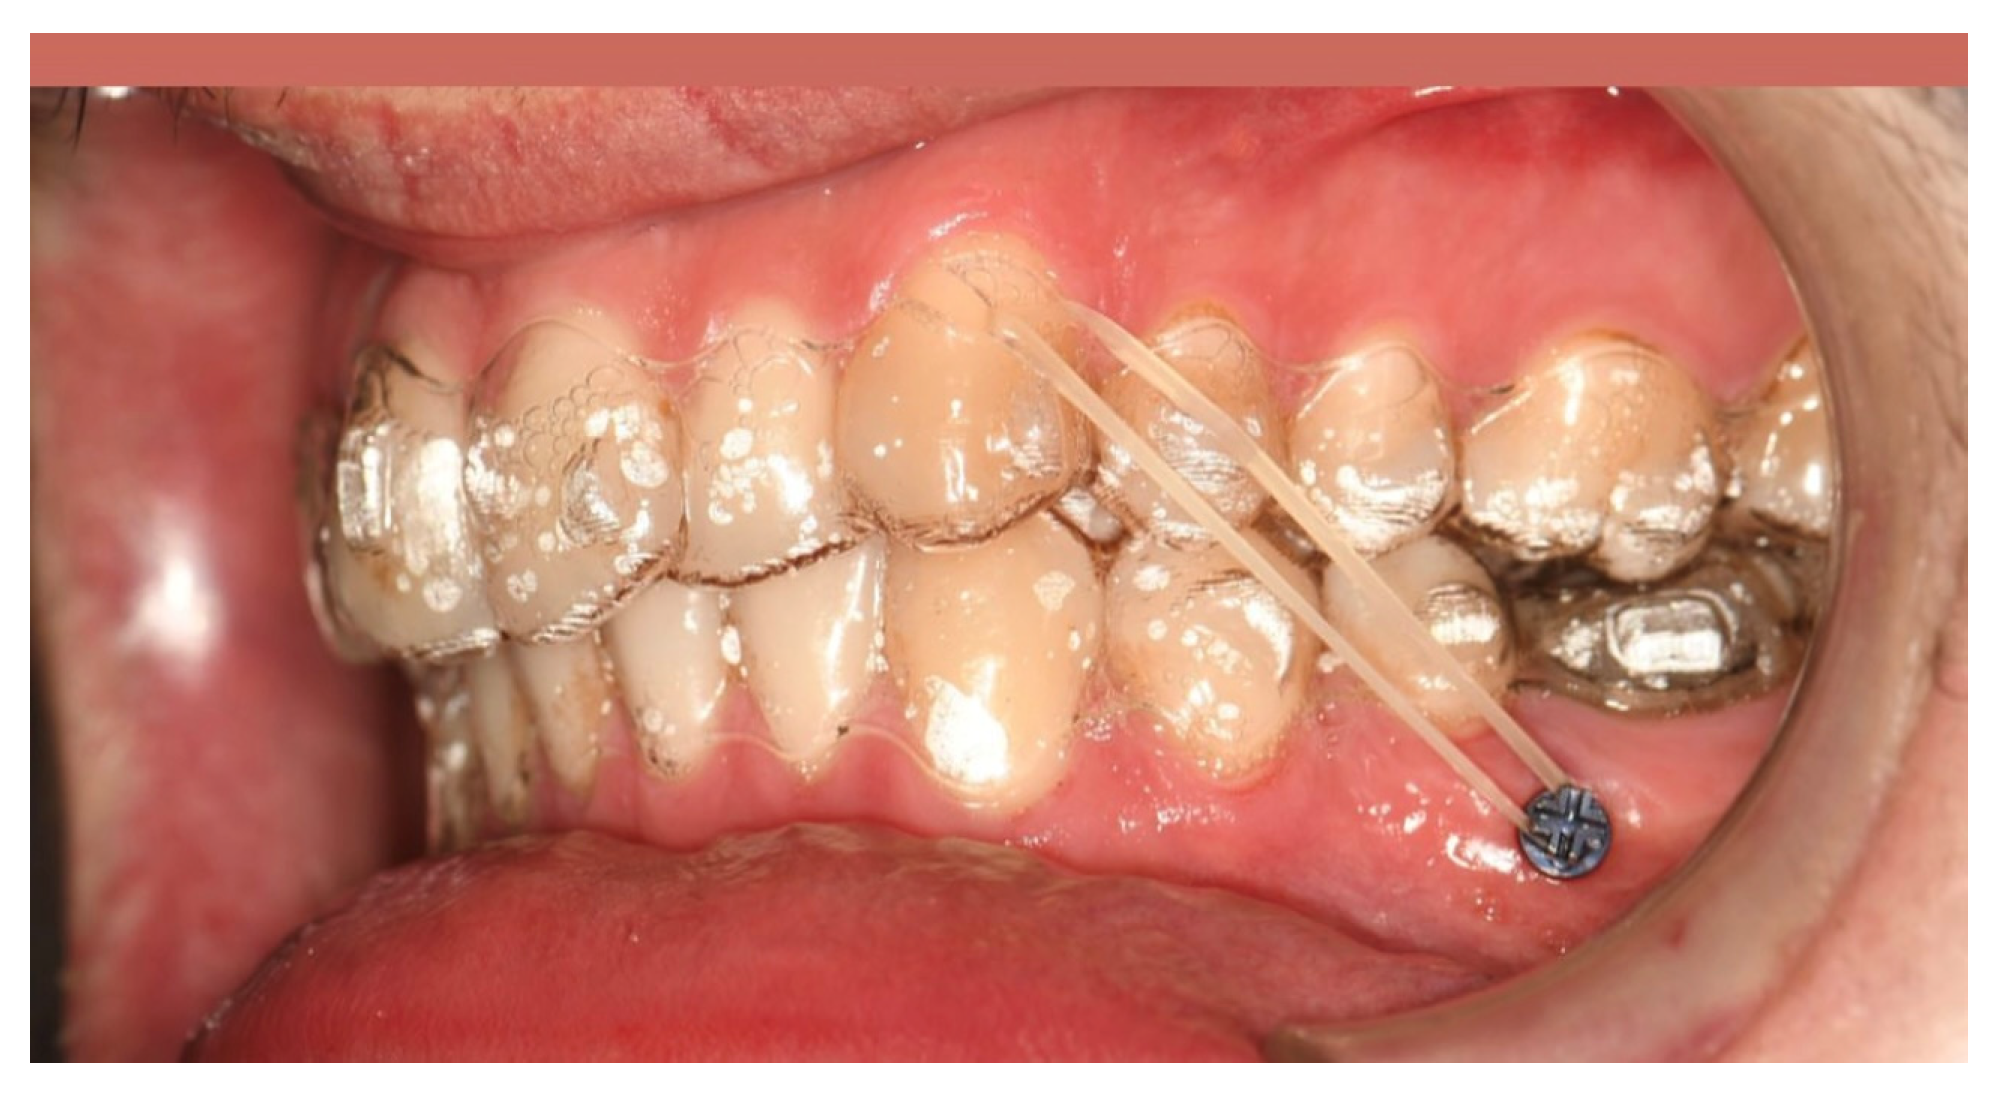

4.1.11. Carriere Distalizer

4.2.2. Buccal Miniscrew-Assisted Distalization Applications

- Yin, K.; Han, E.; Guo, J.; Yasumura, T.; Grauer, D.; Sameshima, G. Evaluating the treatment effectiveness and efficiency of Carriere Distalizer: A cephalometric and study model comparison of Class II appliances. Prog. Orthod. 2019, 20, 24. [Google Scholar] [CrossRef]

| Yin et al. (2019) [42] | Tooth tissue-supported | Carriere distalizer | 3.5 mm distal movement of first molars and 3 mm protrusion of upper anterior teeth | 150–200 g from the Class II elastics | 6.3 months | 0.62 mm of premolars and anchorage loss in the mandibular dental arch due to Class II elastics | There is no clinically significant skeletal correction caused by the Carriere distalizer in growing patients. |